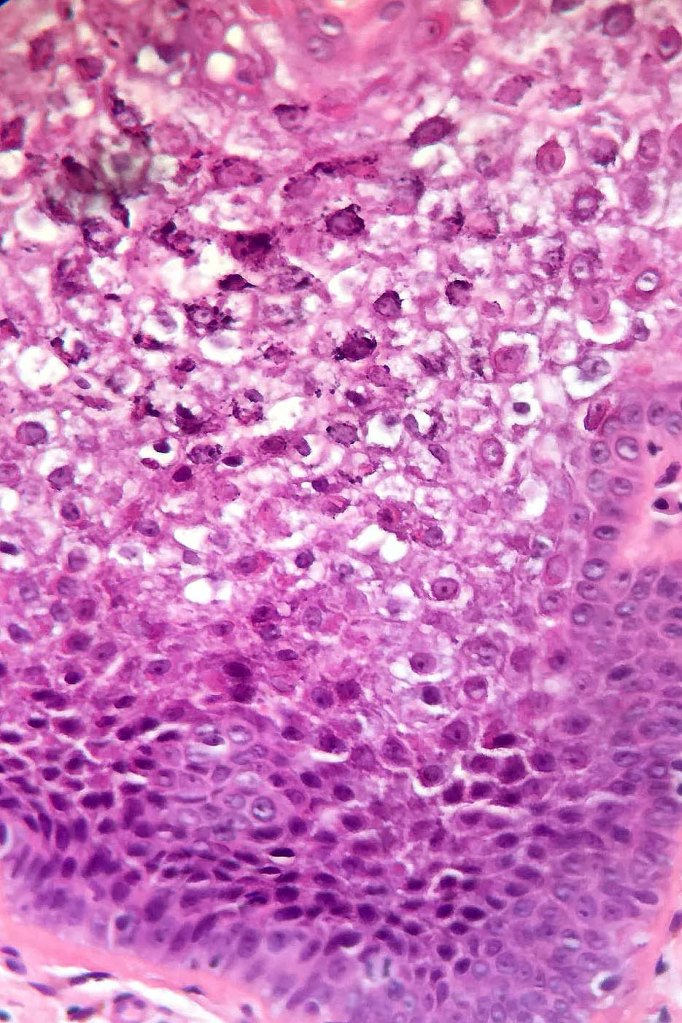

•Superficial epidermis shows often multifocal keratinocyte vacuolation with eosinophilic cytoplasmic inclusions & sometimes epidermal necrosis